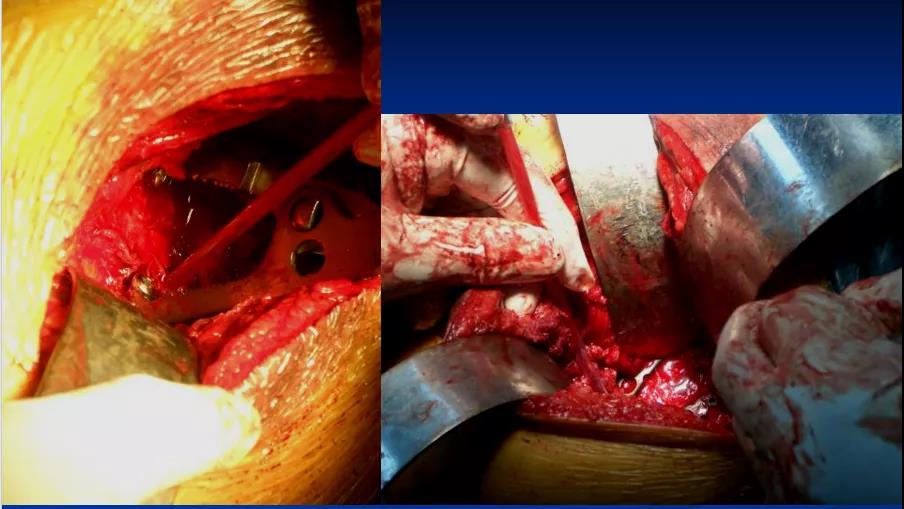

2、一般先选择骨折移位大、粉碎较严重的后柱后壁骨折一侧 3、常先采取Kocher-Langenbeck后入路切口,改半俯卧位;切口:髂后上棘外下4cm处→经大转子顶点→ 垂直向下约5cm, 显露后柱后壁骨折

4、 以骨撬分别放在髂棘、坐骨大切迹、坐骨小切迹,显露后柱后壁骨折

5、根据CT情况探查关节腔,清除关节内的碎骨片; 6、a:解剖复位髋臼后柱及后壁;b:以重建钢板固定 c:纱布填塞切口 d:行C型臂透视了解前壁或前柱骨折复位情况;

7、后柱后壁解剖复位后,由于关节囊完整,前柱一般都能自然复位,对于后柱复位后,前柱骨折移位仍明显且复位该部位能明显修复整个髋臼的解剖序列和减少术后并发症的枢纽部位作为前入路的切开部位。前入路微创切口沿髂耻嵴插板,行前柱重建钢板内固定;

8、若采取前路髂腹股沟入路,改半仰卧位;切口:髂嵴和耻骨联合上;2 cm 两部位取切口;腹股沟区域不予切开显露

9、根据需要分别暴露前壁及前柱骨折部位:术中注意避免损伤髂腰肌及股神经束、髂外血管、精索或圆韧带死亡冠动脉

10、沿髂耻嵴插板,在耻骨上支用2枚螺钉固定,维持前柱,前壁解剖序列连续性,再髂骨上固定另一枚螺钉,起到断端加压作用。